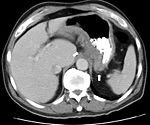

Radiologic tests

A small bowel follow-through may suggest the diagnosis of Crohn's disease and is useful when the disease involves only the small intestine. Because colonoscopy and gastroscopy allow direct visualization of only the terminal ileum and beginning of the duodenum, they cannot be used to evaluate the remainder of the small intestine. As a result, a barium follow-through x-ray, wherein barium sulfate suspension is ingested and fluoroscopic images of the bowel are taken over time, is useful for looking for inflammation and narrowing of the small bowel. Barium enemas, in which barium is inserted into the rectum and fluoroscopy used to image the bowel, are rarely used in the work-up of Crohn's disease due to the advent of colonoscopy. They remain useful for identifying anatomical abnormalities when strictures of the colon are too small for a colonoscope to pass through, or in the detection of colonic fistulae.

CT and MRI scans are useful for evaluating the small bowel with enteroclysis protocols.They are additionally useful for looking for intra-abdominal complications of Crohn's disease such as abscesses, small bowel obstruction, or fistulae. Magnetic resonance imaging (MRI) are another option for imaging the small bowel as well as looking for complications, though it is more expensive and less readily available